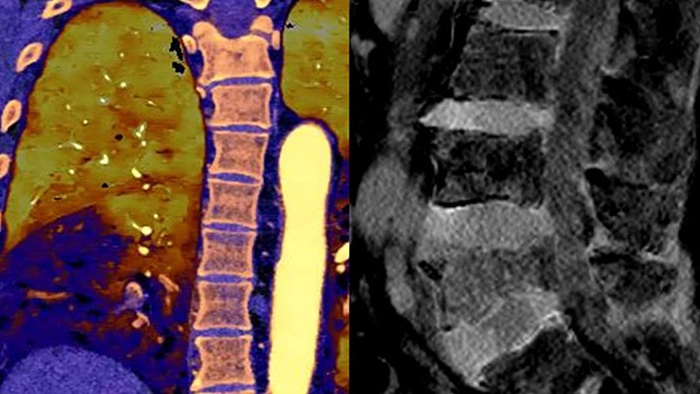

Unlike traditional CT images, spectral-detector CT images capture spectral information 100% of the time —without special planning or set-up. That means you can analyze the spectral data in any image retrospectively, using a variety of spectral viewing tools. You can, for example, adjust the monoenergetic level or get Zeffective maps.

Spectral detector simultaneously absorbs and differentiates high and low energy from a single polyenergetic X-ray beam. Spectral results are acquired within a single scan without the need for special modes.

Spectral CT helps me objectively differentiate contrast staining from hemorrhage, obviating the need for additional follow up scanning and prolonged patient observation, which can result in reduced costs and radiation exposure to patients.1,2

Ryan K. Lee, MD

Chair of the Department of Radiology, Einstein Healthcare Network